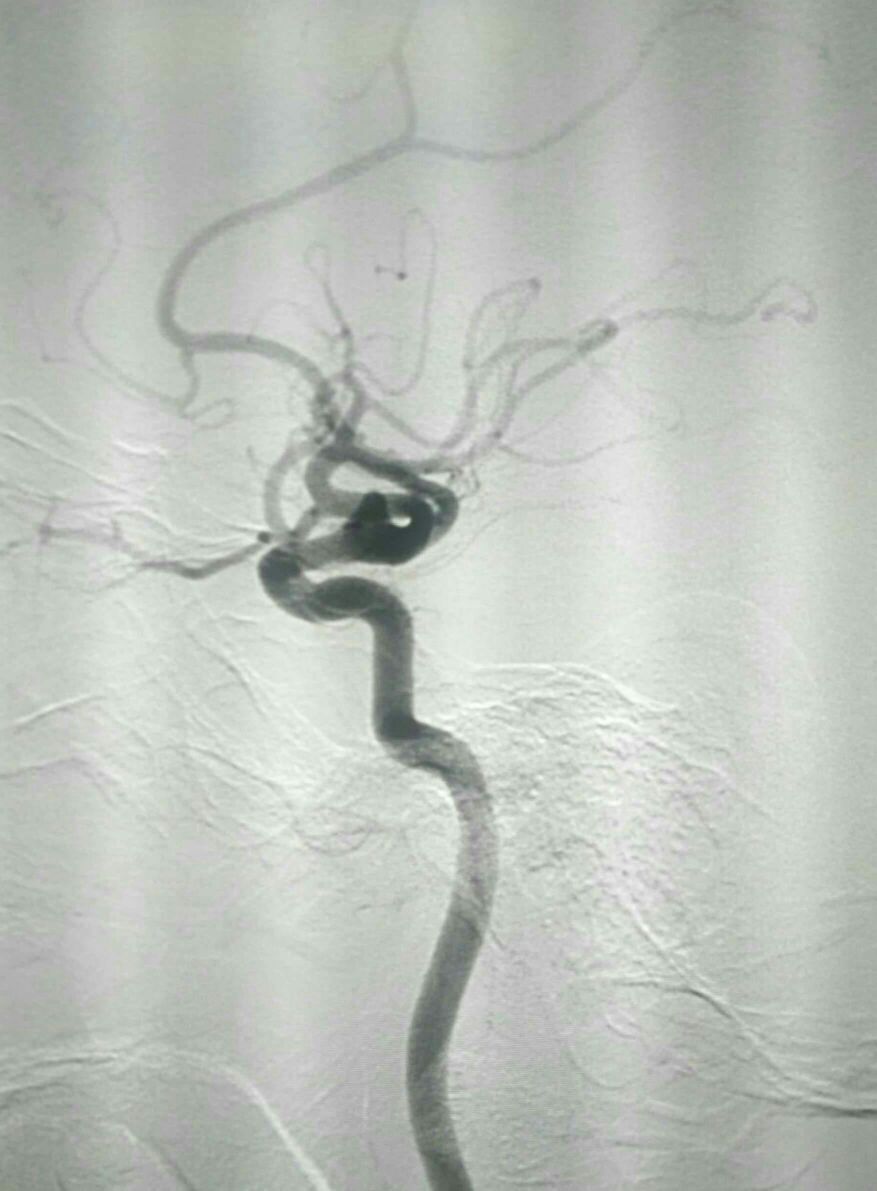

正位像栓塞影像满意

果不其然,动脉瘤栓塞部位急性血栓形成波及同侧大脑中动脉闭塞导致左侧半球急性缺血表现。

可见原双层支架打开良好